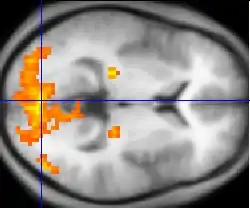

A fMRI scan showing regions of activation in orange, including the primary visual cortex (V1, BA17)

Functional MRI (fMRI) measures signal changes in the brain that are due to changing neural activity. It is used to understand how different parts of the brain respond to external stimuli or passive activity in a resting state, and has applications in behavioral and cognitive research, and in planning neurosurgery of eloquent brain areas.[48][49] Researchers use statistical methods to construct a 3-D parametric map of the brain indicating the regions of the cortex that demonstrate a significant change in activity in response to the task. Compared to anatomical T1W imaging, the brain is scanned at lower spatial resolution but at a higher temporal resolution (typically once every 2–3 seconds). Increases in neural activity cause changes in the MR signal via T*

changes;[50] this mechanism is referred to as the BOLD (blood-oxygen-level dependent) effect. Increased neural activity causes an increased demand for oxygen, and the vascular system actually overcompensates for this, increasing the amount of oxygenated hemoglobin relative to deoxygenated hemoglobin. Because deoxygenated hemoglobin attenuates the MR signal, the vascular response leads to a signal increase that is related to the neural activity. The precise nature of the relationship between neural activity and the BOLD signal is a subject of current research. The BOLD effect also allows for the generation of high resolution 3D maps of the venous vasculature within neural tissue.